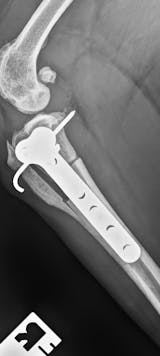

The first photo was taken five months post-surgery, and the second is just one month into using the laser. You can see a big difference already, the crack on the right side has fully healed, and there’s noticeable progress on the left side of the plate as well.

She’s definitely feeling better too, keen to do so much more! But for now, it’s still leash walks and pen rest while she continues to heal.

It’s been a long road, and she sadly had to spend the whole summer on strict rest. But fingers crossed, by next summer she’ll be ready to live life to the fullest again. 💛